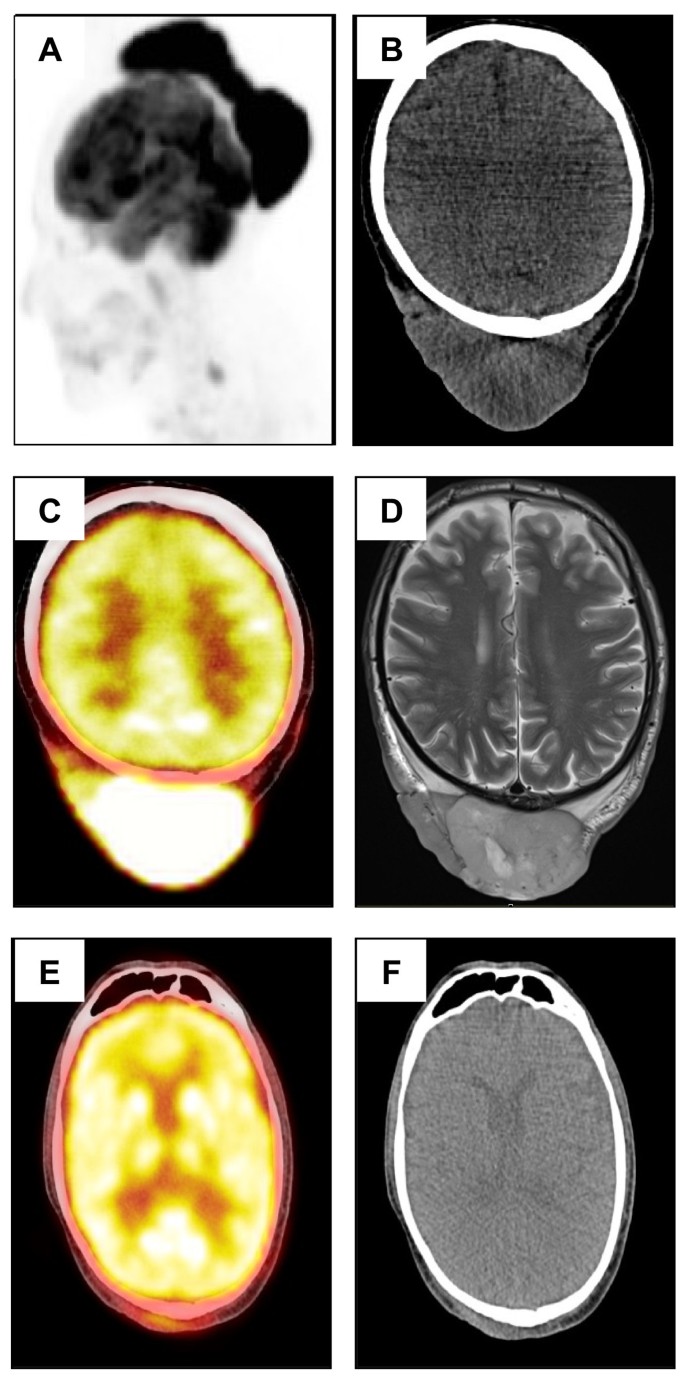

实验目的:明确患者的临床表型及肿瘤累及范围。方法细节:56岁男性,头皮出现19×16×4 cm多结节肿块,面部伴发类似病变;行MRI和PET/CT检查。结果解读:MRI显示头皮巨大肿瘤(图3A、3B),PET/CT提示肿瘤代谢活跃(图3C、3D),右侧颈部可疑淋巴结,无全身播散。产品关联:文献未提及具体影像学产品,领域常规使用西门子、GE的MRI设备及飞利浦的PET/CT设备。

实验目的:评估R-CHOP-21对PCFCL的疗效及对ET的影响。方法细节:给予4周期R-CHOP-21化疗(利妥昔单抗+环磷酰胺+阿霉素+长春新碱+泼尼松),随后放疗;随访2年。结果解读:2周期后肿瘤缩小90%(图1B、3E-F),2年无复发;ET未缓解,血小板计数稳定在600-700×10^9/L,仅用阿司匹林预防。产品关联:化疗药物未提及品牌,领域常规使用罗氏的利妥昔单抗、Baxter的环磷酰胺等。